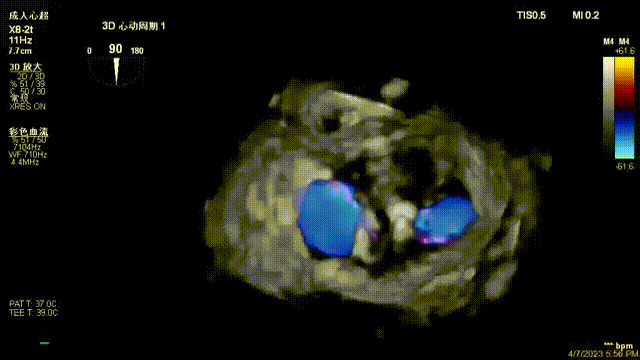

接受治療的是一例器質(zhì)性重度二尖瓣反流(DMR)患者,主訴“反復(fù)活動后胸悶,氣促3年余”。術(shù)前超聲顯示,雙房增大,二尖瓣脫垂伴重度反流,輕度三尖瓣反流,輕度肺高壓,升主動脈增寬。手術(shù)經(jīng)股靜脈-房間隔入路,采用全身麻醉插管,在TEE和DSA引導(dǎo)下完成房間隔穿刺。置入JensClip瓣膜夾系統(tǒng)后,在左房調(diào)整瓣膜夾的位置和軸向,后進(jìn)入左室,在TEE引導(dǎo)下捕捉二尖瓣前后瓣葉,并關(guān)閉瓣膜夾。經(jīng)TEE反復(fù)確認(rèn)手術(shù)效果后最終鎖定并釋放瓣膜夾。術(shù)后即刻超聲顯示瓣膜夾位置穩(wěn)定,功能良好,術(shù)前二尖瓣反流4+,術(shù)后0反流,肺靜脈逆流和左房壓都顯著好轉(zhuǎn),手術(shù)圓滿成功(以上數(shù)據(jù)都來源于醫(yī)院的臨床記錄)。術(shù)后患者狀態(tài)良好,目前已安排出院。

出院前隨訪超聲